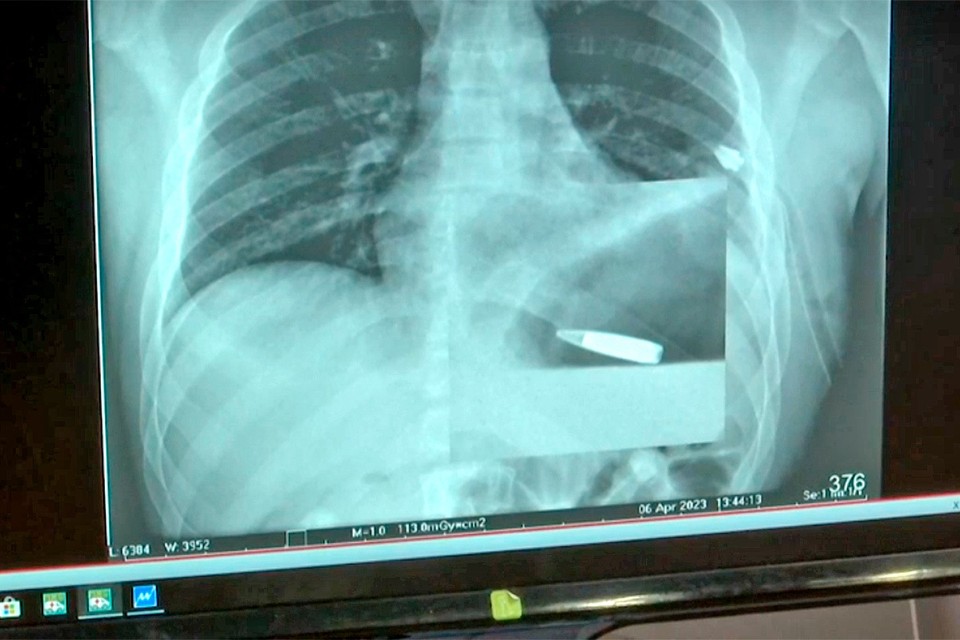

Герой спецоперации «Z» полковник Лищук достал из сердца сержанта пулю снайпера

В ЦВКГ им. Вишневского провели уникальную операцию по извлечению пули из сердца воина, что был ранен на передовой украинским снайпером kp.ru »